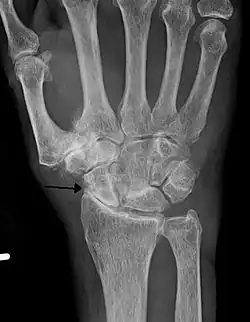

Severe osteoarthritis and osteopenia of the carpal joint and 1st carpometacarpal joint -